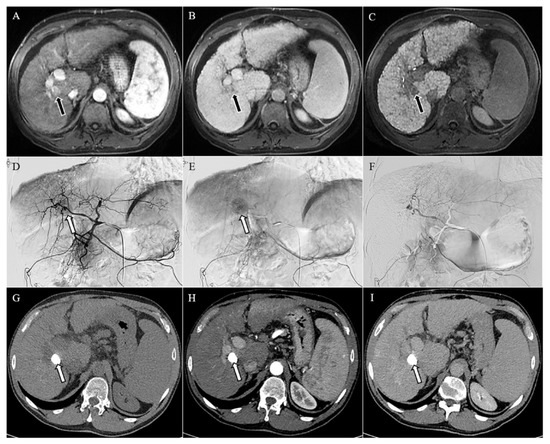

- Renzulli, M.; Peta, G.; Vasuri, F.; Marasco, G.; Caretti, D.; Bartalena, L.; Spinelli, D.; Giampalma, E.; D’Errico, A.; Golfieri, R. Standardization of conventional chemoembolization for hepatocellular carcinoma. Ann. Hepatol. 2021, 22, 100278. [Google Scholar] [CrossRef]